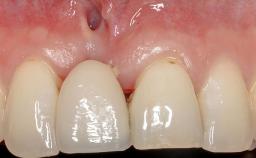

Early Implant Placement, Contour Augmentation, and Autologous Connective-Tissue Graft Using a Tunneling Technique to Replace an Upper Incisor with Generalized Gingival Recession

Variations in soft-tissue volume, evidenced either by an overabundance (Evian and coworkers 1993; Levine and McGuire1997; Dolt and Robbins 1997) or by a deficiency of soft or hard tissue can complicate implant-supported rehabilitations in the esthetic zone (Lorenzana 2008; Lorenzana and coworkers 2009). The present case illustrates the replacement of a failing upper left lateral incisor complicated by generalized severe gingival recession in the esthetic zone.

| Abutment Type | CAD/CAM |

| Prosthesis Type | FDP |